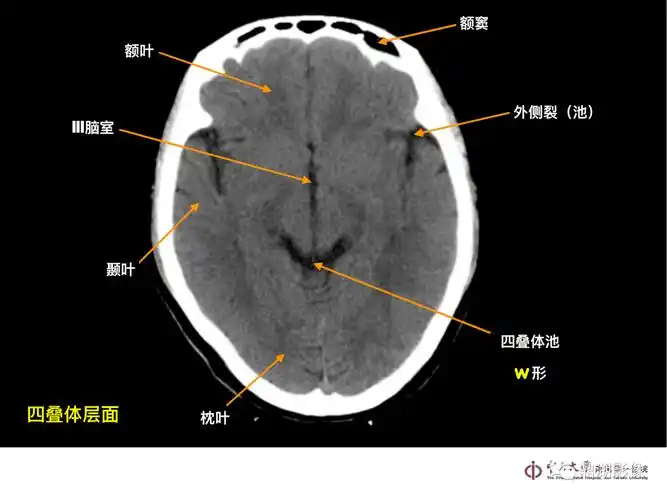

影像总结头颅ct基本知识与常见病变